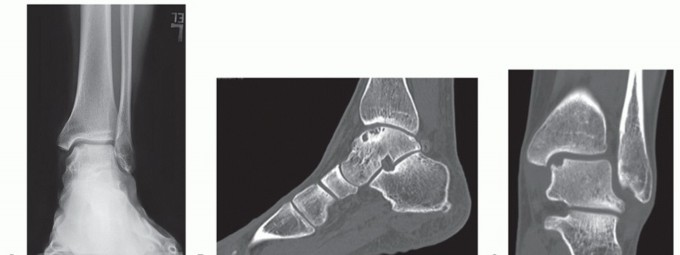

DEFINITION Tibiotalocalcaneal arthritis is formally defined as the loss of cartilage from both the tibiotalar…